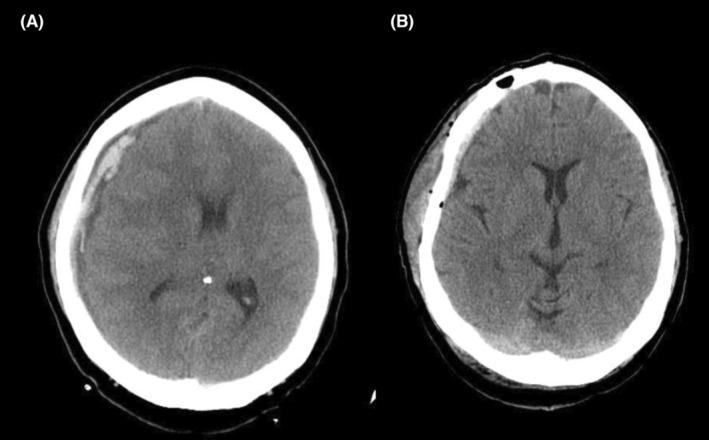

创伤后脊髓空洞症患者颅颈交界区蛛网膜松解术后急性幕上硬膜下血肿;病例报告及文献复习

Acute supratentorial subdural hematoma after craniocervical junction arachnolysis in a patient with posttraumatic syringomyelia; case report and literature review.

In patients with SAA rapid CSF drainage while performing durotomy must be avoided by utilizing cotton pads and lowering the head level to avoid catastrophic complications.

摘要